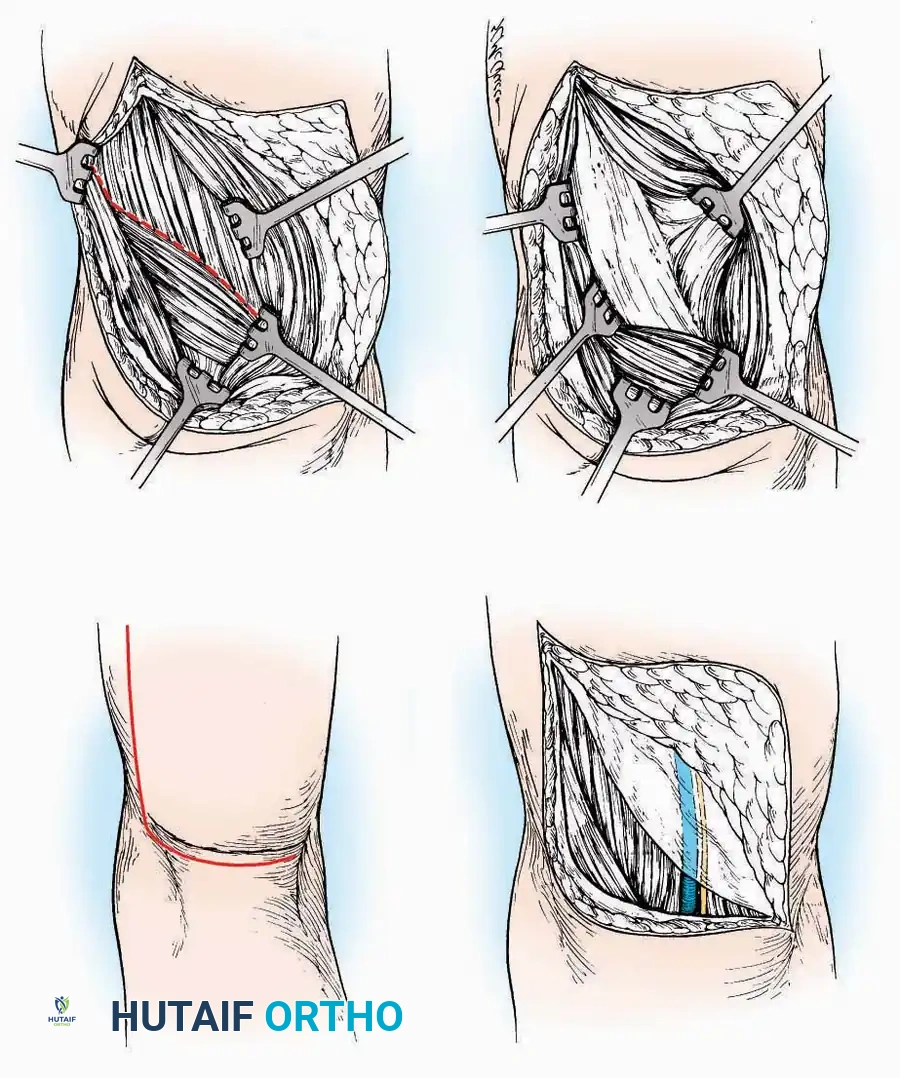

Anterior Approach

Indications: Total ankle arthroplasty (TAA), anterior ankle arthrodesis, and excision of anterior tibial/talar osteophytes (anterior impingement).

💡 Clinical Pearl

Gaining access to the medial gutter (the articulation between the medial malleolus and the medial articular facet of the talus) can be challenging through a pure anterior approach. Meticulous medial subperiosteal dissection of the joint capsule is required to avoid excessive traction on the anterior neurovascular bundle.

Surgical Technique:

* Incision: Make a 10 to 15 cm longitudinal incision over the anterior aspect of the ankle, centered exactly midway between the medial and lateral malleoli.

* Superficial Dissection: Incise the superficial fascia. Identify and protect the superficial peroneal nerve branches laterally and the saphenous nerve medially.

* Internervous Plane: The deep dissection exploits the plane between the Extensor Hallucis Longus (EHL) tendon (innervated by the deep peroneal nerve) and the Extensor Digitorum Longus (EDL) tendons (also innervated by the deep peroneal nerve).

* Neurovascular Bundle: Incise the extensor retinaculum. Carefully identify the anterior tibial artery and the deep peroneal nerve, which typically lie between the EHL and EDL, or directly deep to the EHL. Retract the neurovascular bundle laterally with the EDL, or medially with the EHL, depending on the specific anatomical variant encountered (lateral retraction is most common).

* Capsulotomy: Incise the anterior joint capsule longitudinally. Elevate the capsule subperiosteally from the anterior tibia and the talar neck to expose the entire tibiotalar articulation.